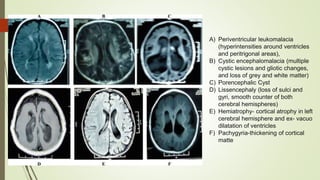

The document discusses autism spectrum disorders (ASD) and cerebral palsy, detailing their definitions, epidemiology, causes, diagnostic criteria, and neurodevelopmental implications. ASD is characterized by social communication deficits and restricted behaviors, while cerebral palsy involves movement and posture disorders resulting from non-progressive disturbances in the developing brain. Various diagnostic tools and treatment methods are highlighted, including behavioral interventions and the importance of early screening.